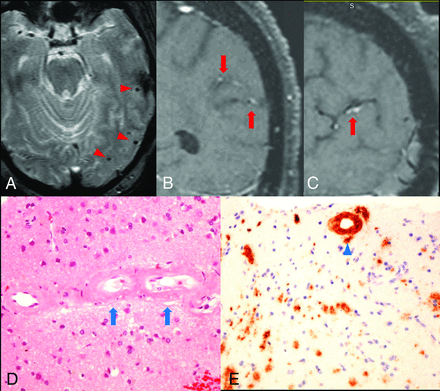

A 75-year-old patient with a history of hypertension, diabetes, progressive memory loss, and behavior changes during 6 months presented with worsening of mental status followed by seizures and status epilepticus. The initial neurologic examination re-vealed impaired attention and language; however, cranial nerves, motor strength, and gait were unremarkable. The patient had fluctuating mental status during the first 3 days and developed a clinical seizure on the fourth day with subsequent nonconvulsive status epilepticus, which was revealed on video-electroencephalography and required multiple antiepileptic agents. MR imaging showed no acute infarction but a few chronic microhemorrhages (Fig 1A) and some white matter changes. Due to the presence of chronic microhemorrhages, the differential diagnosis of vasculitis or amyloid angiopathy was entertained. Conventional angiography showed normal intracranial arteries. VWMRI (3D T1-weighted fast-spin-echo sequence with variable refocusing flip angle acquisition with inherent black-blood effect [sampling perfection with application-optimized contrasts by using different flip angle evolution, SPACE sequence; Siemens, Erlangen, Germany]: FOV, 230 mm; TR/TE, 700/18 ms; matrix, 256 mm2; 144 sections × 0.9-mm thick; voxels, 0.9 × 0.9 × 0.9 mm3) on the eighth day of admission showed arterial wall enhancement along the cortical branches of the left middle cerebral artery in the left parietal and temporal lobes (Fig 1B, -C). Findings of clinical and laboratory work-ups were negative for CNS infection, systemic vasculitis, or metabolic abnormalities except for elevated blood glucose (340 mg/dL on admission). Biopsy revealed β-amyloid accumulation in the vessel wall without associated inflammation (Fig 1D, -E).

Arterial wall enhancement is associated with amyloid accumulation within the vessel wall. A, Gradient-echo image shows microhemorrhages in the left temporal lobe (red arrowheads). B and C, coronal and sagittal views of postcontrast T1-weighted VWMRI show enhancement in the wall of cortical branches of the left middle cerebral artery in the parietal and temporal lobes (red arrows). D, Hematoxylin-eosin stain of a left temporal lobe sample shows thickened, hyalinized blood vessels containing amorphous eosinophilic material (blue arrows) in small- and medium-sized arteries within the leptomeninges and superficial cortical gray matter. E, Immunostain for β-amyloid shows amyloid accumulation within the vessel wall (blue arrowhead). No inflammatory cells were observed surrounding the vessels.